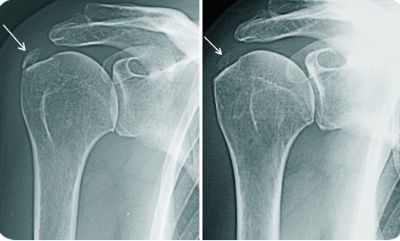

Для диагностики используют:

- рентгенографию в двух проекциях;

Для диагностики периартрита обычно используют рентгенографию, УЗИ, МРТ, КТ, артрограмму и клинический анализ крови. Также проводят дифференциальную диагностику с тромбофлебитом вен верхних конечностей, диффузным васкулитом, дерматитом, опоясывающим лишаем и другими заболеваниями.